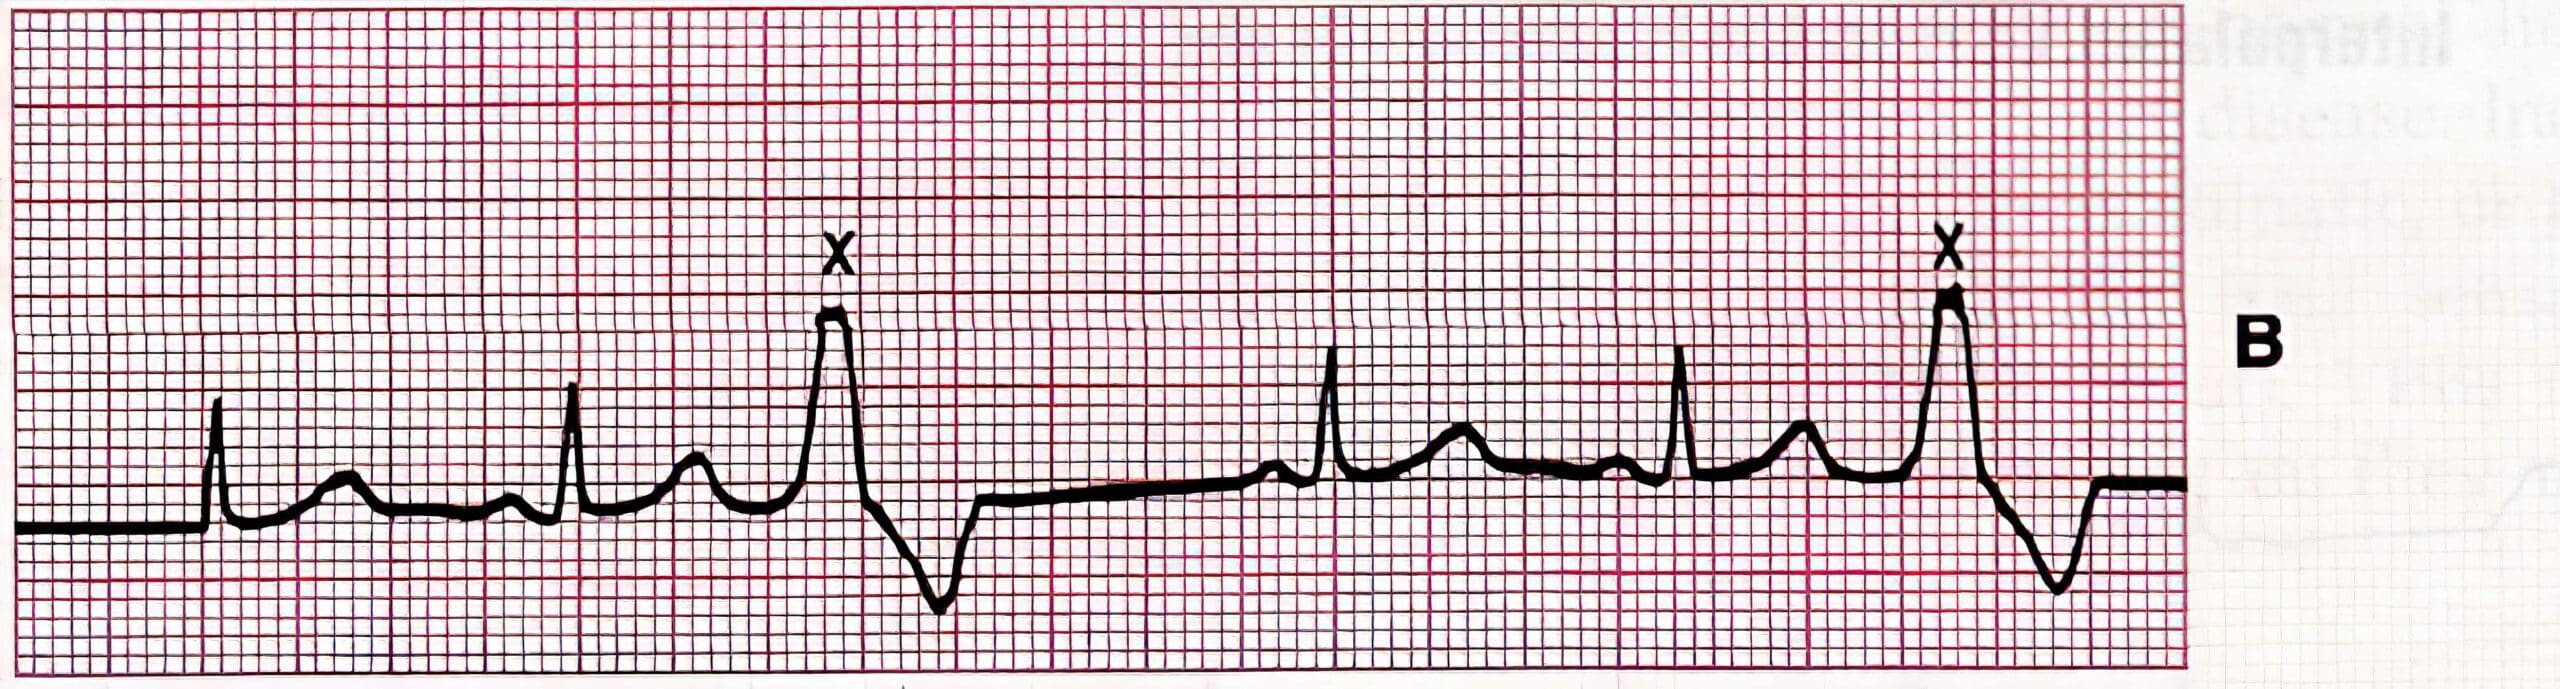

Period of Vulnerability and R-on-T Phenomena: T waves coincide with the repolarization of the ventricle. During this time, there is a period that is absolutely refractory followed by a period that is relatively refractory to another depolarization. In the former, no depolarizations can occur. However, in the latter, the cells are somewhat unstable considered to be in a period of vulnerability.

Traditionally, a PVC during the vulnerable period was thought to lead to unstable ventricular tachycardias such as VF or VT. However, research now suggests that PVCs occurring at any time during the cardiac cycle can lead to these arrhythmias. Instead, certain factors may lead to VF or VT, such as a long QT interval due to electrolyte imbalances or drug overdoses.

In patients with a predisposing condition, a prolonged R interval (due to bradycardia) can incite a PVC, which then superimposes on the T wave (R-on-T phenomena). This may then initiate polymorphic VT (e.g., torsades de pointes).

PVC With Prolonged RR Interval Leading to V-Tach or VF